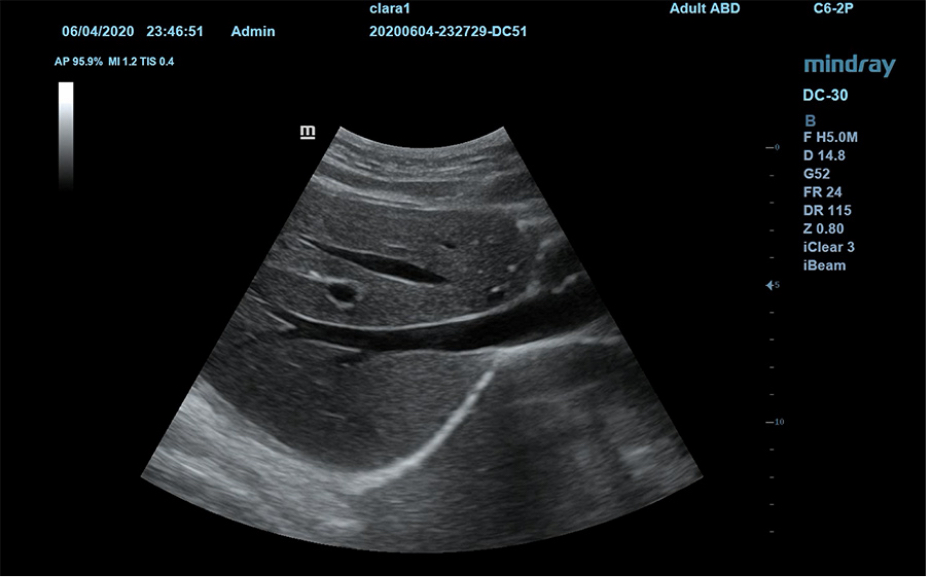

1Широкий выбор плоскостей исследования для конкретных случаев.

Пакеты плоскостей, охватывающие различные области применения: брюшная полость, акушерство и гинекология, щитовидная железа, молочная железа, яички.

Широкий выбор плоскостей исследования для конкретных случаев

Пакеты плоскостей, охватывающие различные области применения: брюшная полость, акушерство и гинекология, щитовидная железа, молочная железа, яички.